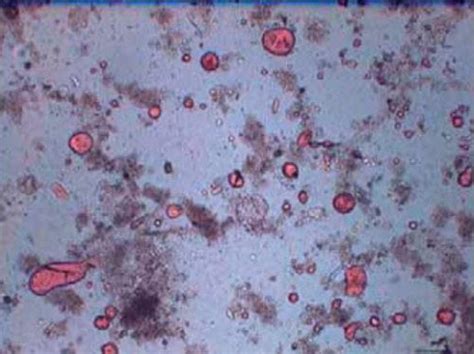

Fecal Fat Test (Qualitative) Uses a dye to stain the stool and identify the presence of excess fat droplets under a microscope.

• fat in stool under microscope